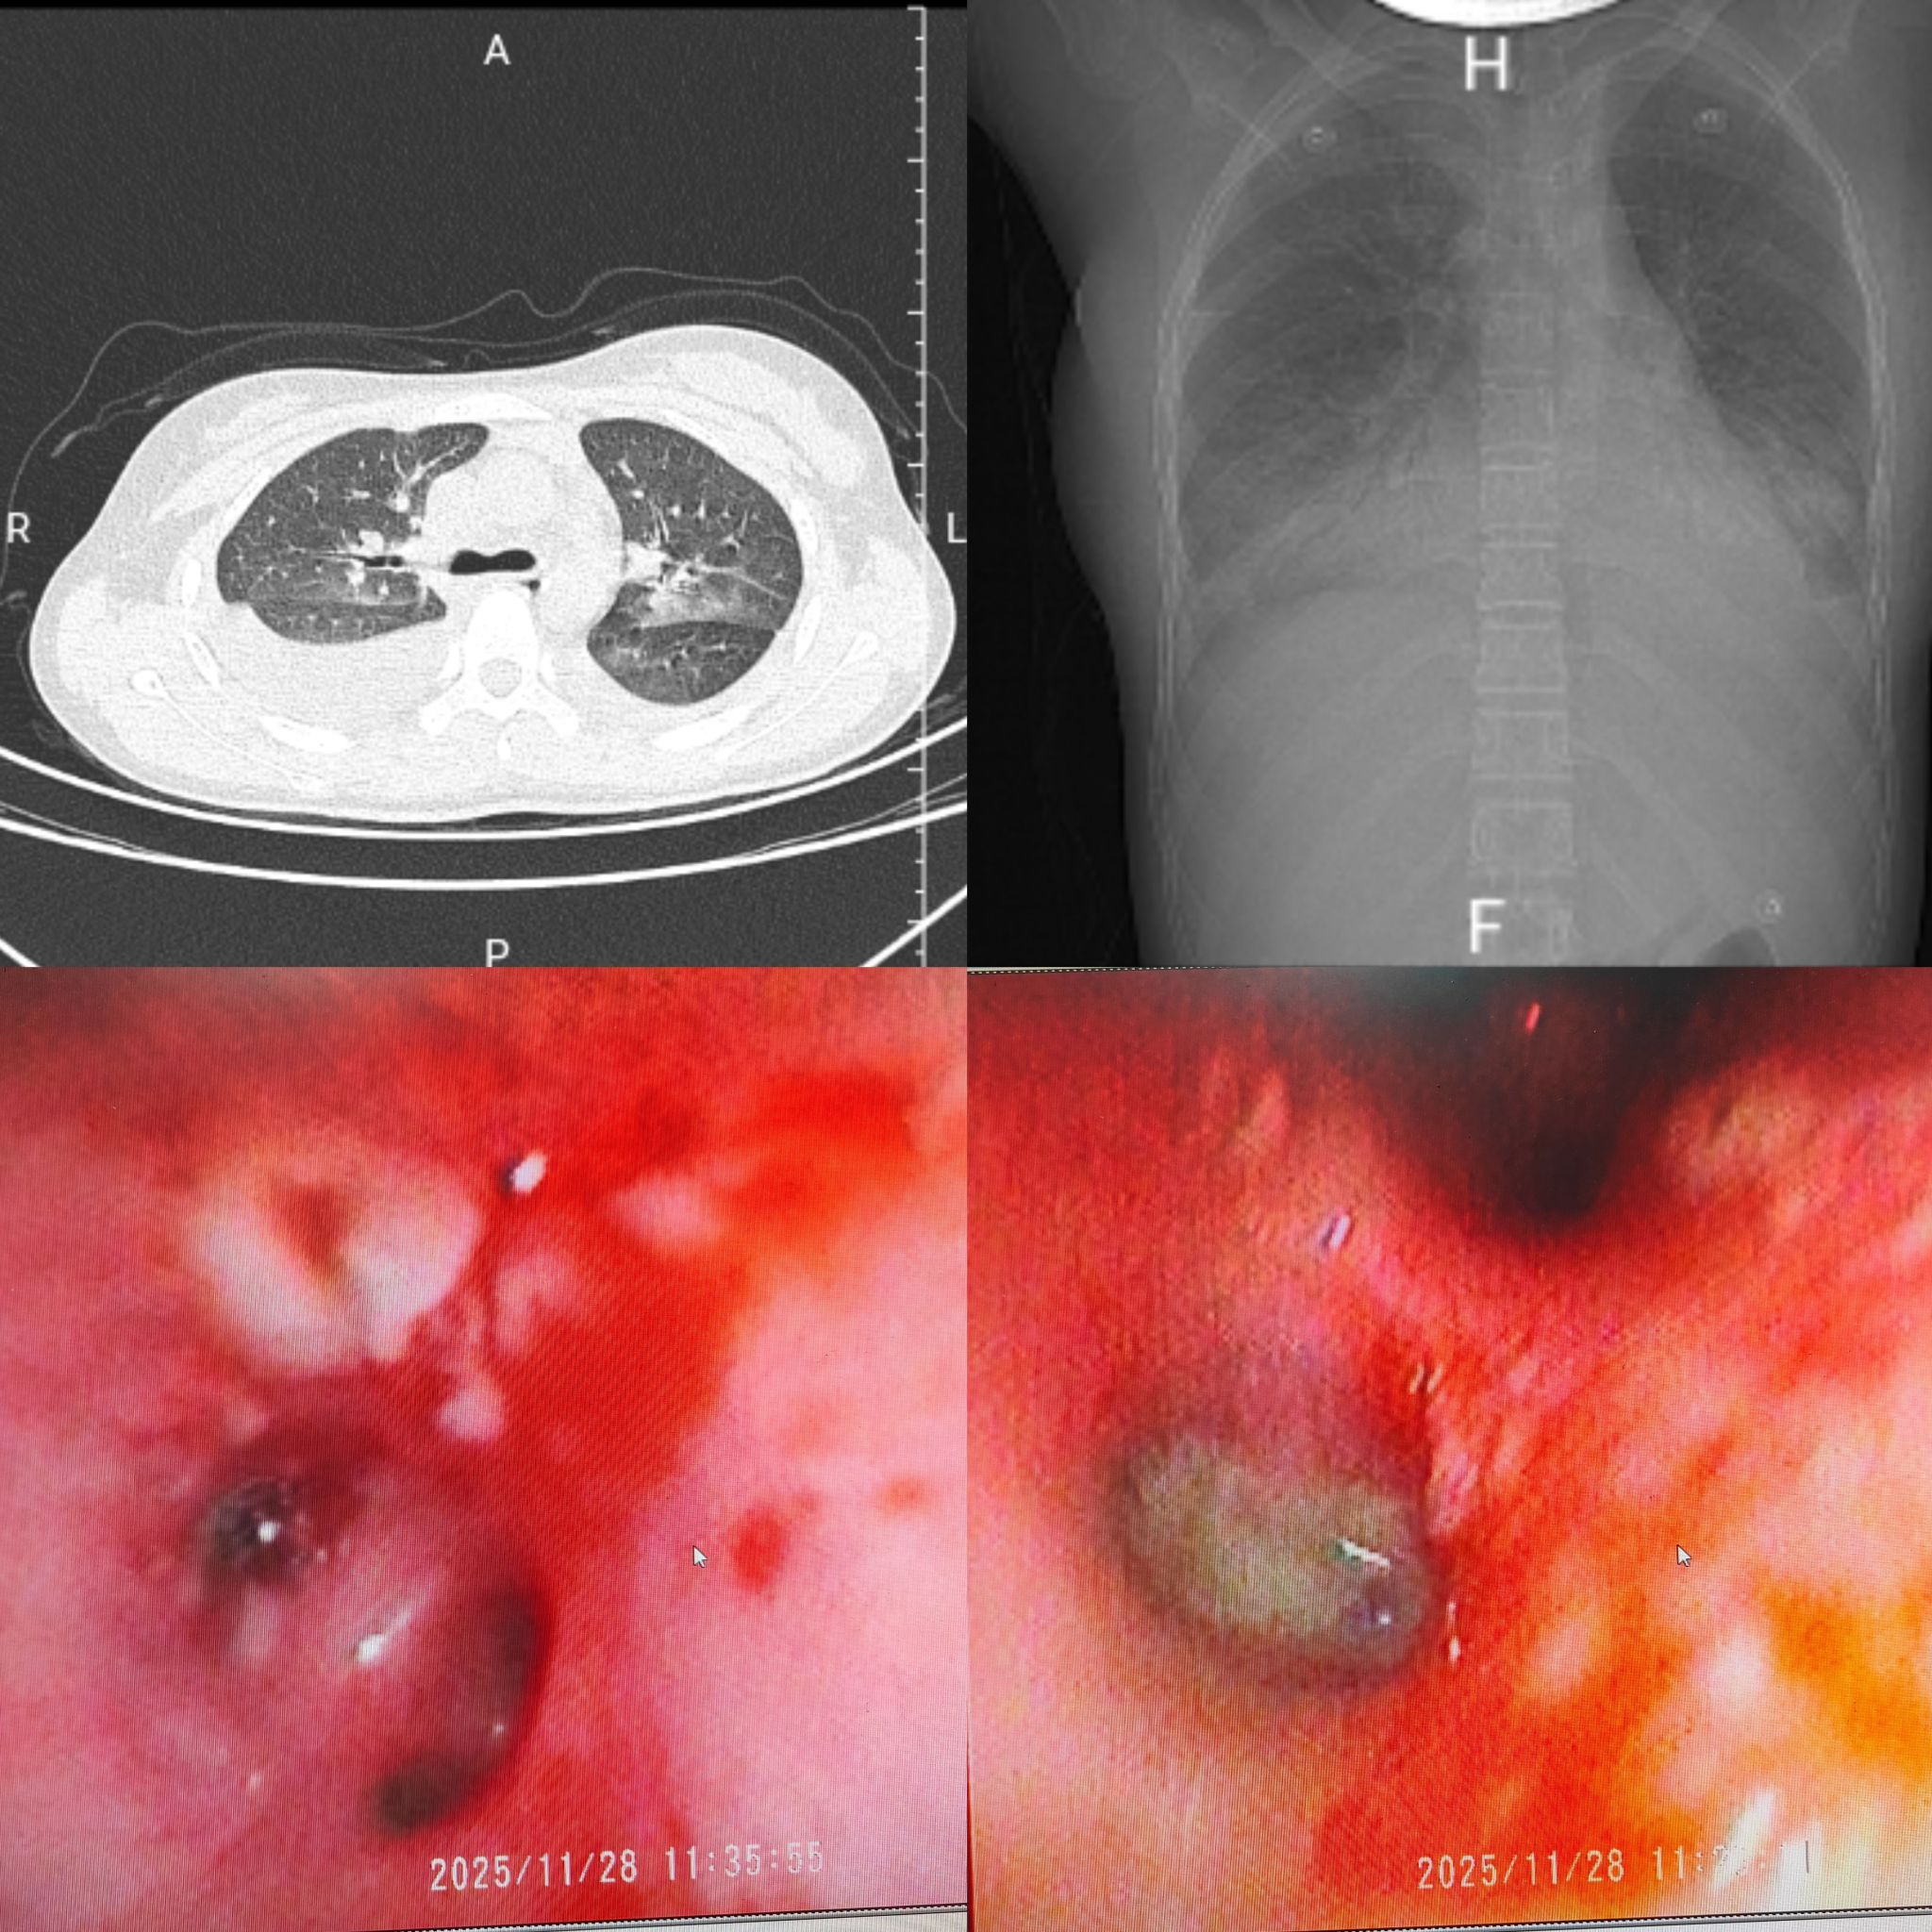

治疗前胸部CT及支气管镜下表现

该患者因严重呼吸困难、间断发热1周不退于午夜由急诊科紧急转入,入院时患儿已出现明显缺氧表现,鼻导管3L/min吸氧下,仍表现出乏力、胸痛、端坐呼吸等重度呼吸窘迫症状,生命体征极不稳定。PICU迅速集结多学科团队,启动重症救治绿色通道,为患儿争取黄金救治时间。医疗团队快速完成胸部CT、病原学及凝血功能等关键检查,精准判定其为流感病毒感染引发的重症肺炎脓毒症,且合并多脏损伤,随时可能因呼吸衰竭、凝血功能崩溃危及生命而进展为多器官功能衰竭。针对患儿病情,PICU团队迅速制定中西医综合救治方案,给予呼吸支持,启动抗感染及免疫调节集束化治疗,通过床旁纤支镜清除气道分泌物,改善肺通气功能,用宣白承气汤合葶苈大枣泻肺汤、清瘟败毒饮等方剂,以清泻泄热、化痰平喘、通腑逐瘀。

经过24小时紧急救治,患儿呼吸困难症状逐渐减轻,氧合、凝血指标趋于稳定。36小时体温下降,48小时体温、凝血指标恢复正常,胸片显示胸水及实变明显吸收。120小时复查胸部CT,肺部实变、胸水基本消失。168小时各项指标均达正常水平,后续经中医巩固治疗,顺利出院。出院后,医院将对患儿实行危重症全周期随访管理,持续筑牢生命安全防线。